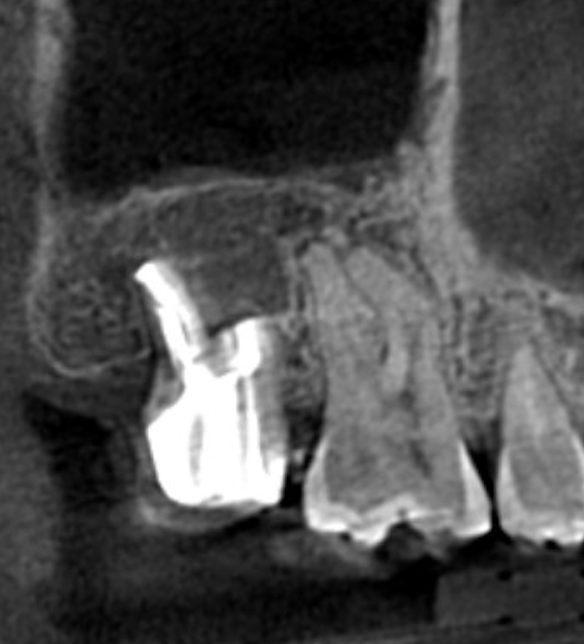

■ 術後経過

術後の経過観察において、

レントゲンおよびCTにて術前と比較を行いました。

その結果、

- 根尖部の透過像は縮小し

- 骨の再生が認められました

また臨床的にも、

- 咬合時の違和感は消失

- 日常生活での不快症状も認められない状態

となり、良好に経過しています。

その後も安定した状態が確認できたため、

最終補綴としてセラミッククラウンを装着しました。

現在も問題なく機能しており、

安定した状態を維持しています。